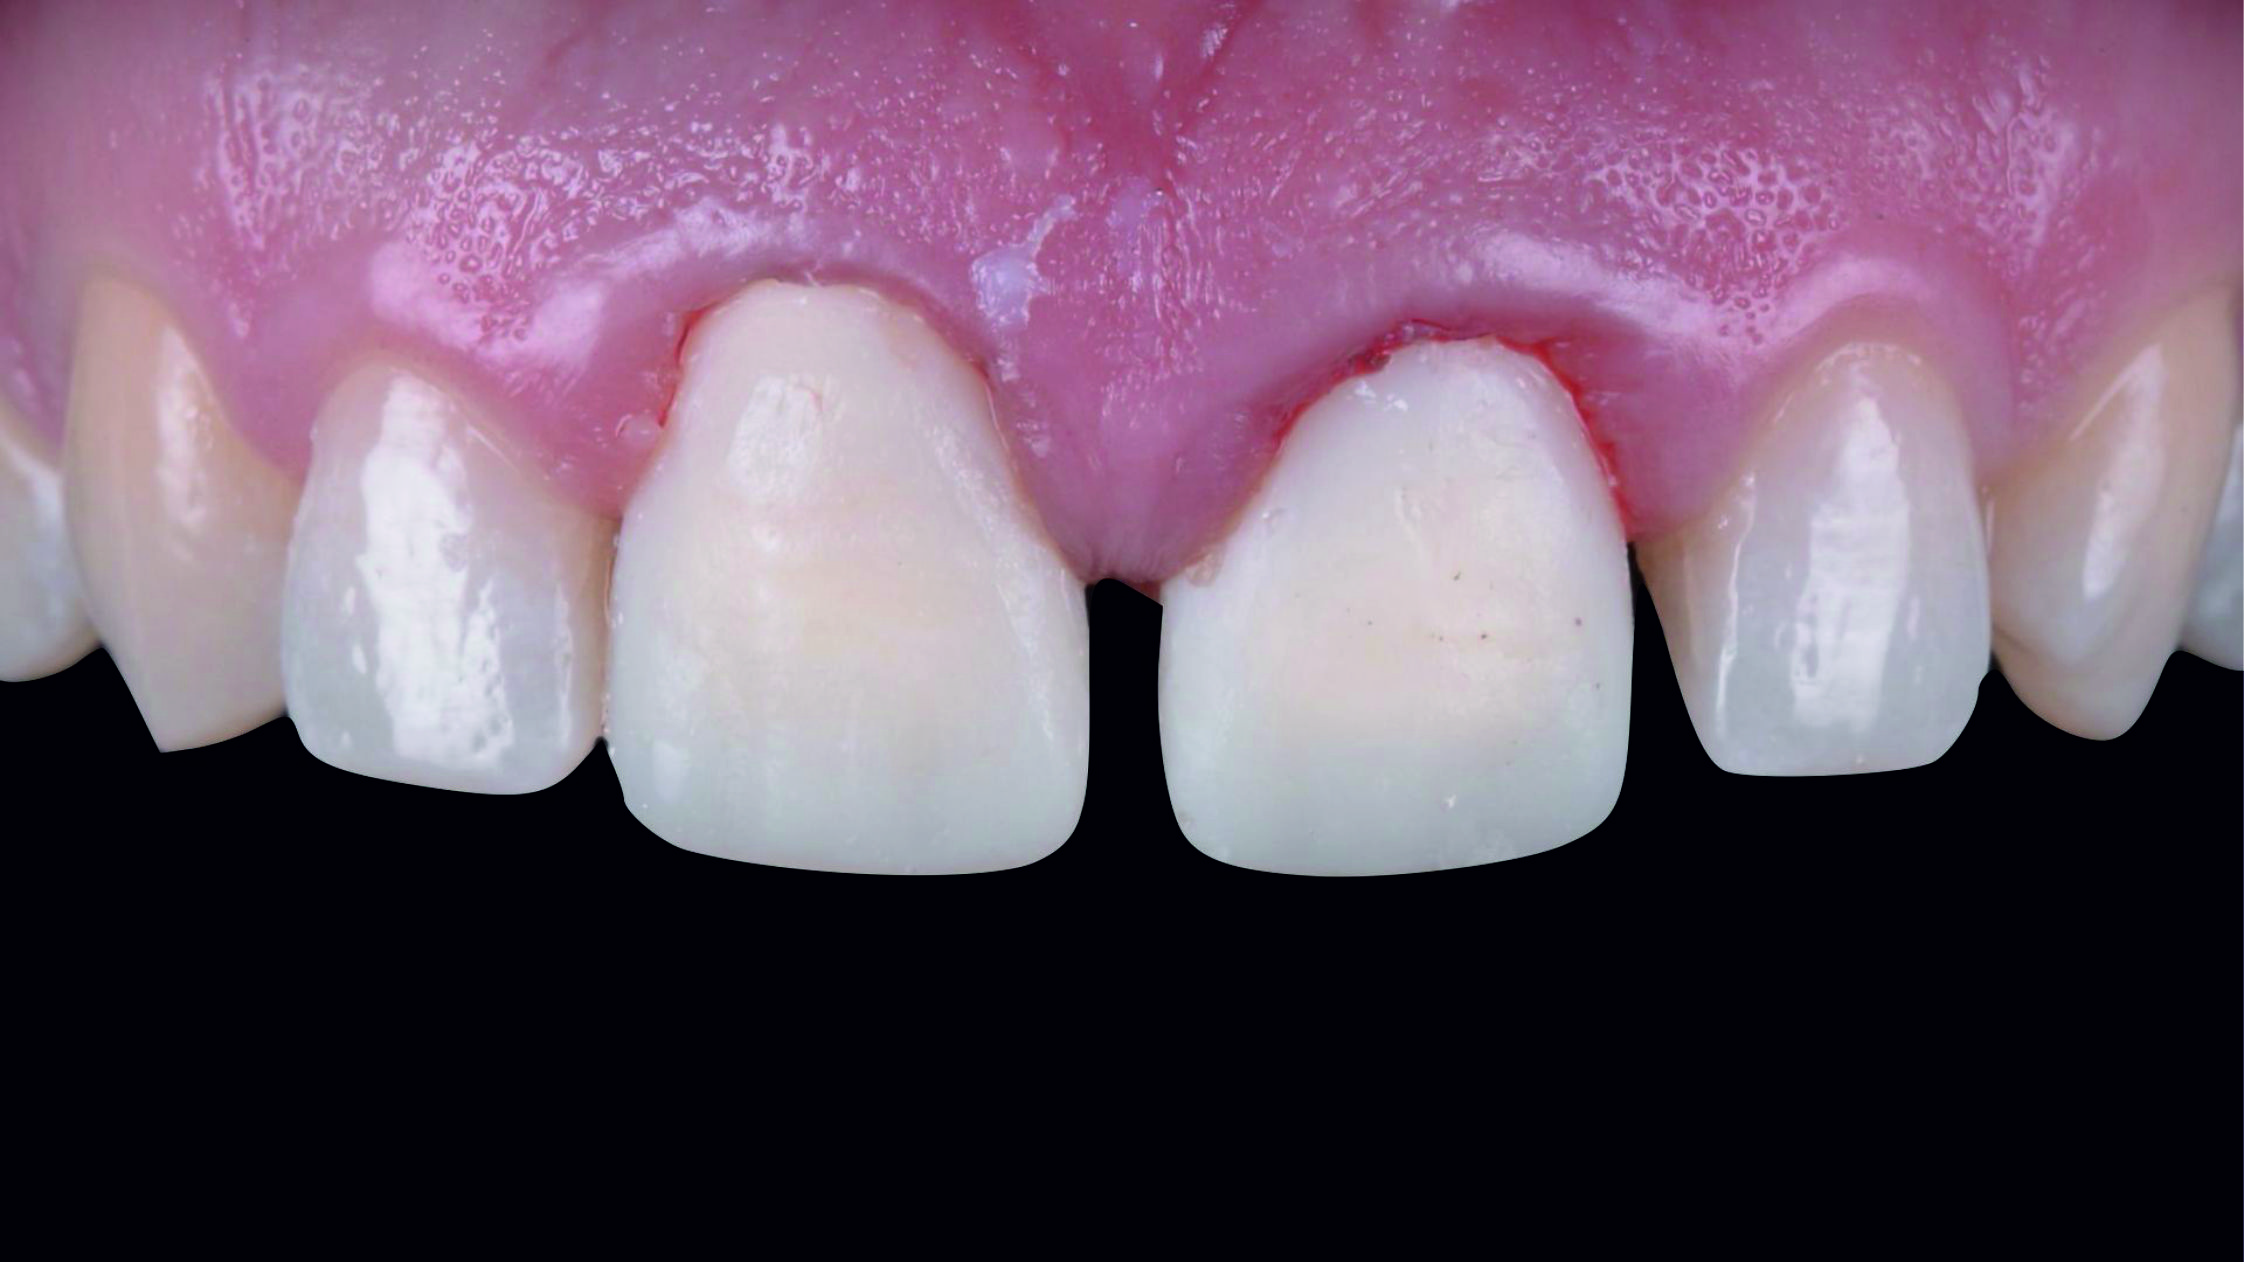

Фото 2. Через високо розташовану лінію посмішки можна припустити, що будь-яка вада після лікування обов'язково буде дуже добре помітною.

Фото 3. Внутрішньоротовий вигляд початкової ситуації.